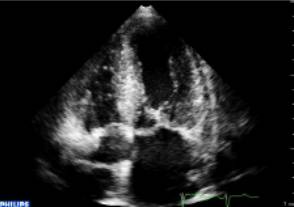

今天小编与大家分享一篇干货:《如何利用超声评价心脏瓣膜和血管?》

首先介绍一下心脏瓣膜的狭窄和反流程度的评价方法。